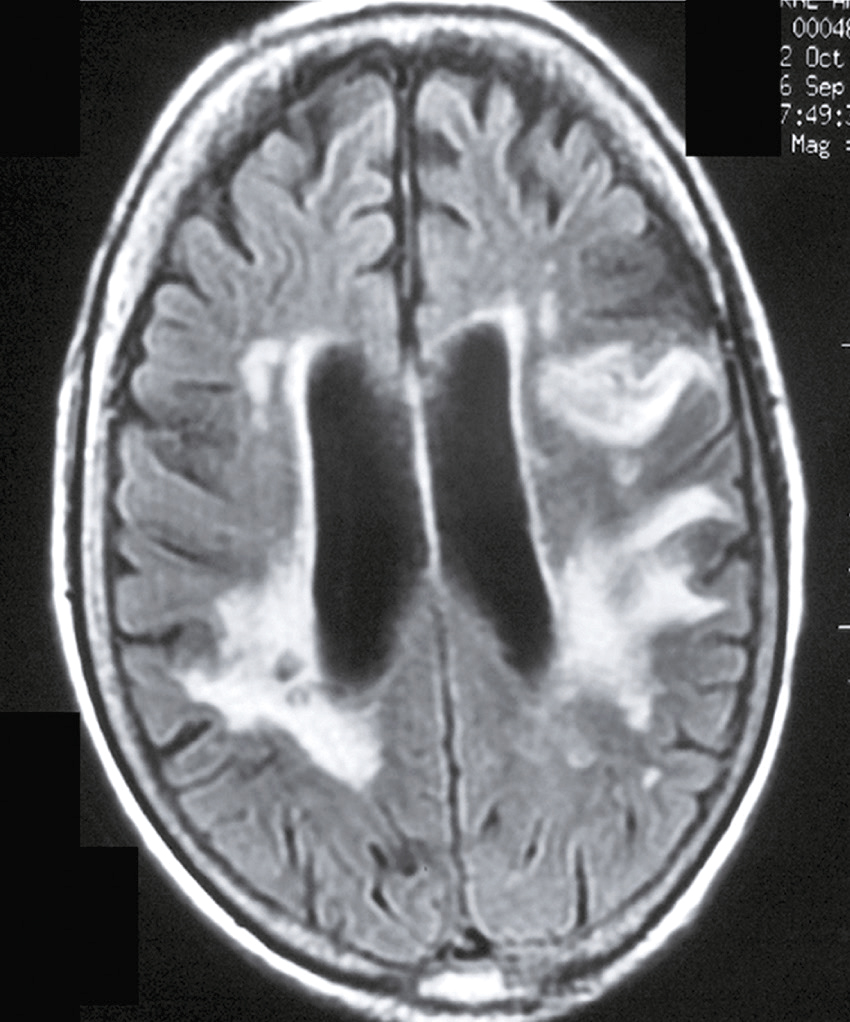

Une nouvelle IRM cérébrale est réalisée devant cette diplopie. Décrivez le cliché (fig. 31.1).

L'image montre une coupe transversale d'un cerveau humain obtenue par imagerie par résonance magnétique (IRM). Cette image est une vue axiale, ce qui signifie qu'elle est prise horizontalement à travers le cerveau. On peut observer les différentes structures cérébrales, y compris la matière grise et la matière blanche. Les ventricules latéraux, qui sont des cavités remplies de liquide céphalo-rachidien, sont visibles au centre de l'image. Les zones plus claires autour des ventricules peuvent indiquer des anomalies ou des lésions, souvent associées à des conditions neurologiques comme la sclérose en plaques. Les contours du cerveau sont bien définis, et les différentes régions du cortex cérébral sont clairement visibles. Cette image est intéressante car elle permet aux médecins de diagnostiquer et de surveiller diverses maladies neurologiques en visualisant les structures internes du cerveau avec une grande précision. L'IRM est une technique non invasive qui utilise des champs magnétiques et des ondes radio pour produire des images détaillées des organes et des tissus internes, ce qui est crucial pour la détection précoce et le traitement des maladies cérébrales.

- C hypersignaux de la substance blanche périventricu-laire

- D hypersignaux du tronc cérébral

- E hypersignaux juxtacorticaux